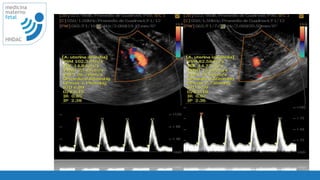

como se

interpreta

• Ea mayor vasodilatacion menor la resistencia del

vaso: <P5%

• Interpretación individualizada

• alteran el doppler

• movimientos

• contracciones uterinas

• corticoides

• lugar de toma de medida

IP menor p5